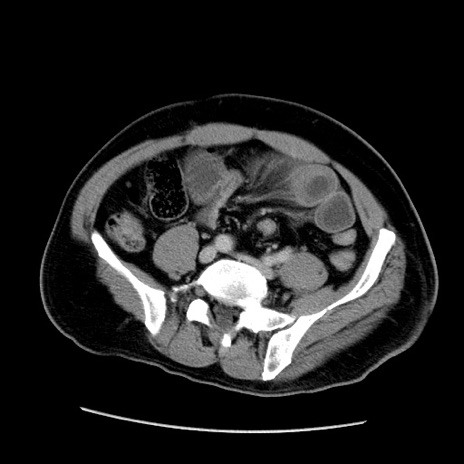

症例22(横断像)

【症例】50歳代男性

【主訴】腹痛

【現病歴】AVMからの被殻出血のため回復期リハ病棟入院中。 本日午後3時頃急に下腹部痛が出現した。

【既往歴】AVM、被殻出血、虫垂炎、高血圧

【身体所見】意識晴明、左半身不全麻痺、会話の理解は良好、36.5°C、腹部:膨隆、全体に板状硬、下腹部正中に圧痛点あり、反跳痛-、筋性防御不明、右下腹部にope scar

【データ】WBC 9400、CRP 0.06